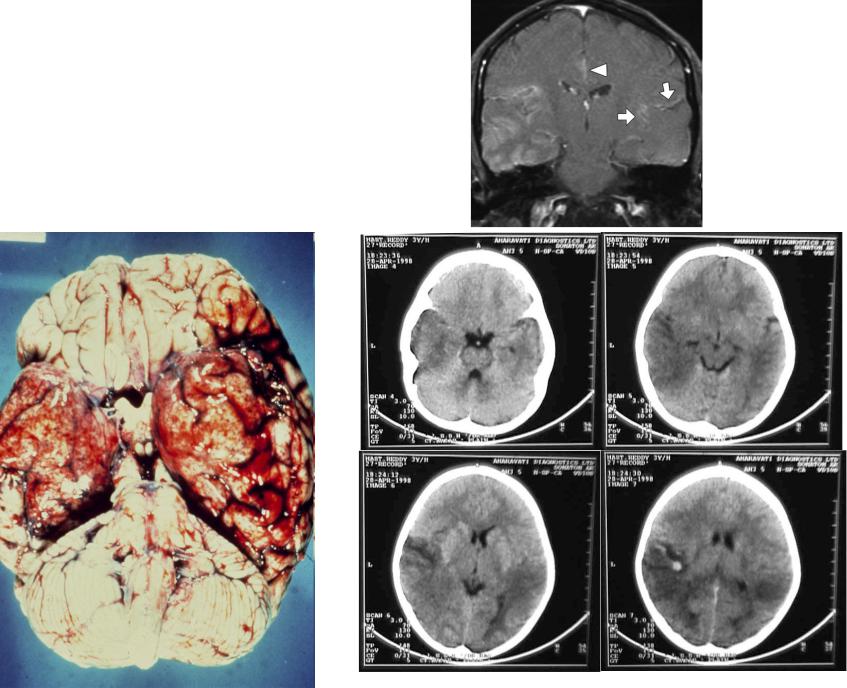

Діагностика: рентген для мозку

Лікарі не ворожать на кавовій гущі: МРТ розкриває набряк, як карту бурі, люмбарна пункція бере ліквор на ПЛР-тест — виявляє ДНК вірусу за години. КТ відсікає інсульт, ЕЕГ фіксує судоми.

У 2026 алгоритм МОЗ: при підозрі — ацикловір одразу, бо чекати — ризик. Антитіла в сироватці доповнюють картину для аутоімунних типів.